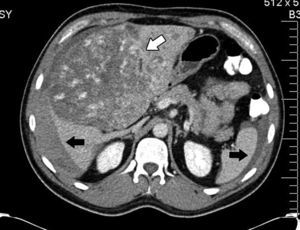

En septiembre presentó hemoptisis y disnea, por lo que se hospitalizo en medio hospitalario particular, en donde se le realizó tomografía axial computada de tórax (fig. 2), broncoscopia con toma de cultivos y biopsias, los cuales fueron negativos a malignidad, tuberculosis o infección fúngica. Se solicita tomografía axial computada de abdomen simple y contrastada donde se muestran lesiones múltiples, redondeadas, hipodensas en el injerto hepático (fig. 3); se toma biopsia guiada por tomografía axial computada, que se reporta negativa a malignidad.

Se realizó autopsia, en la cual se observan tumoraciones redondeadas, vascularizadas en todo el injerto hepático, afectación a porta y arteria hepática (fig. 4), en parénquima pulmonar, múltiples metástasis las cuales forman lesiones pequeñas, con datos hemorrágicos (fig. 5). Además también presentaba metástasis en el bazo, glándulas suprarrenales y páncreas.

El angiosarcoma se presenta con metástasis tempranas a otros órganos como pulmón, bazo o hueso10. En las radiografías simples de tórax pueden encontrarse infiltrados difusos. Los hallazgos más comunes en la tomografía axial computada de tórax por metástasis de angiosarcoma son las lesiones múltiples sólidas, que cuando se presentan con hemorragia dan una imagen de vidrio despulido, que se conoce como signo del halo y ocurre en el 32% de los pacientes. En menor proporción pueden encontrarse cambios quísticos de paredes delgadas (13%) que cuando se distribuyen en las zonas pleurales aumentan la incidencia de neumotórax o hemotórax12.